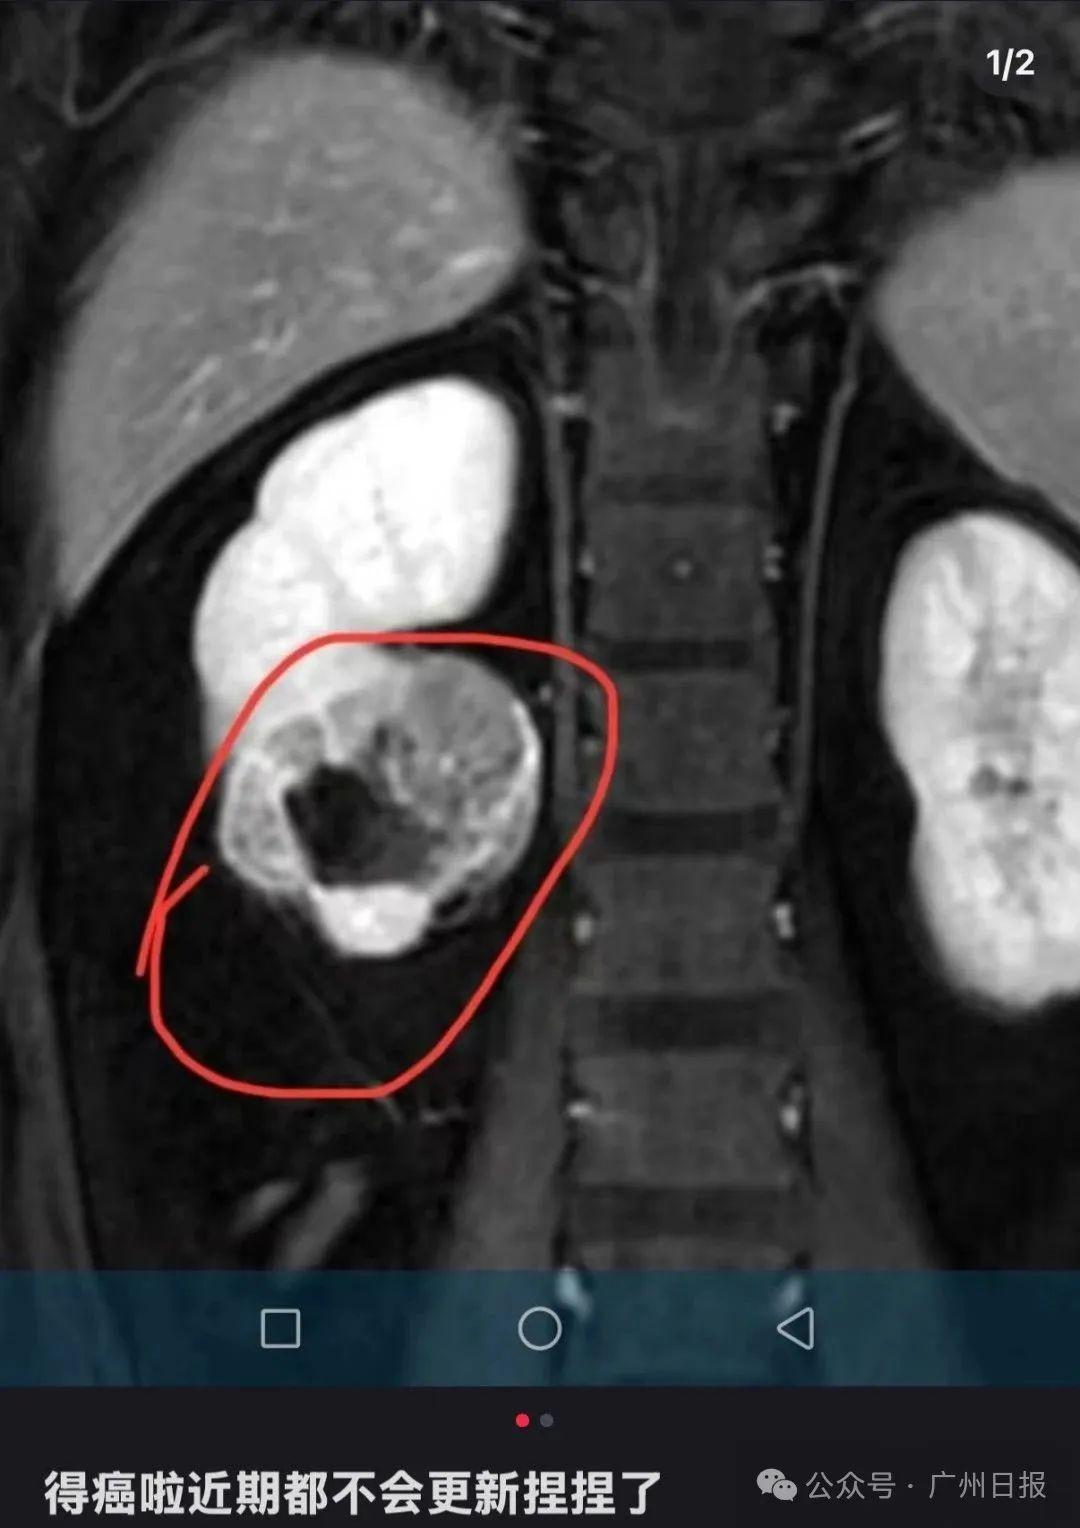

該博主在社交媒體上發文透露自己罹患腎癌,並宣佈將暫時停止更新與“捏捏”玩具相關的視頻內容。該博主最新更新透露病情:腎臟有部分壞死,即將進行手術。

該博主在社交平臺宣佈罹患癌症。圖源其賬號截圖